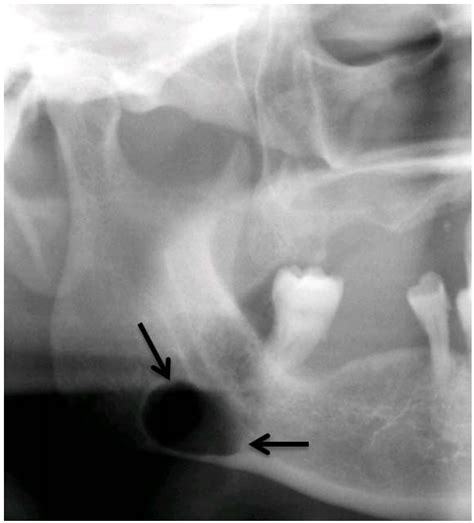

Diagnosis of a traumatic bone cyst typically involves a combination of clinical examination and radiographic imaging. Dental X-rays, such as periapical radiographs or panoramic radiographs, are commonly used to visualize the cyst. In some cases, a computed tomography (CT) scan or magnetic resonance imaging (MRI) may be recommended for a more detailed evaluation.

The radiographic appearance of a traumatic bone cyst can vary, but some common features include:

• Well-defined Radiolucent Lesion: The cyst appears as a well-defined, radiolucent area on dental radiographs.

• Scalloped Margins: The margins of the cyst may be scalloped, giving it a characteristic appearance.

• Cortical Bone Expansion: In some cases, the cyst may cause expansion of the cortical bone.

• No Internal Structures: Unlike other cysts, a traumatic bone cyst typically does not contain internal structures such as septa or calcifications.